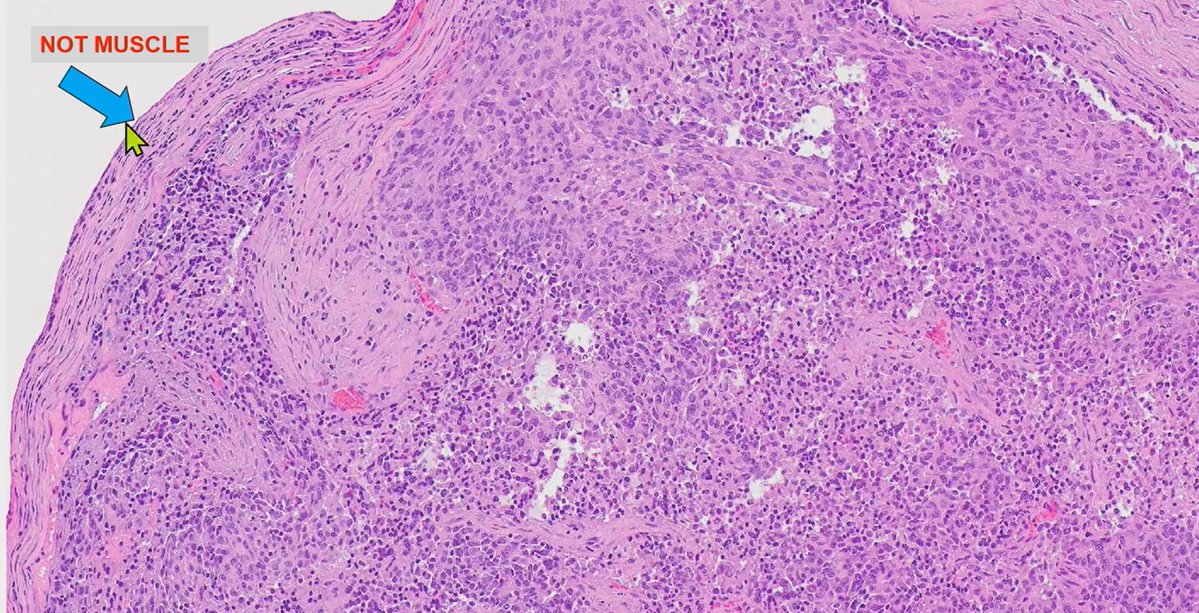

Patients with squamous cell carcinoma and margin evaluation in retromolar trigone -frozen sections pitfall ⚠️

Juxtaoral organ of Chievitz:

- Benign epithelial cords in nerve rich stroma

- Lobulated

- Well circumbscribed nest, cytologically bland

Dr. Nishino- 2025 Diagnostic Pathologic Update #USCAP #pathology #PathX